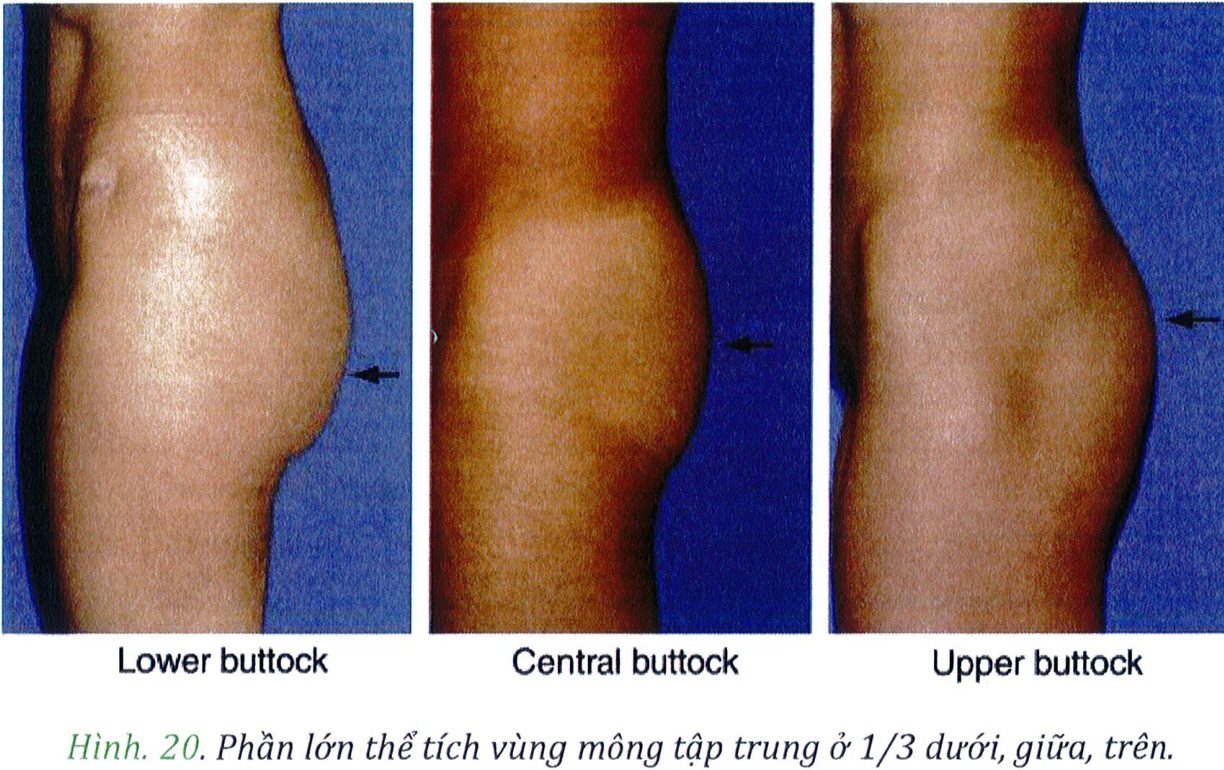

Mặt bên vùng mông có thế được chia thành 3 vùng: trên, giữa, dưới (xem hình 19). Sự phân chia tương ứng với 3 điểm A, B, C và chúng giúp xác định vùng nào được phân bố mỡ nhiều/ít hơn các vùng còn lại. Trong thấm mỹ vùng mông, phần lớn mô mỡ dưới da sẽ nằm ở vùng trung tâm (chính giữa mông), và phần mỡ dưới da còn lại sẽ được phân bố đồng đều ở hai bên. Như vậy chúng ta có thể tưởng tượng ra hình dạng tổng thể của mông khi nhìn từ phía bên là hính chữ C ngược (Hình 19). Có một số tác giả cho rằng điểm nhô ra nhiều nhất của vùng mông sẽ là điểm nằm ngang với xương mu ở tư thế đứng.

Khi làm việc từ góc nhìn bên này, chúng ta cần rõ ràng xác định được đâu là ranh giới vùng mông trên giữa dưới (Hình 20). Việc xác định này rất quan trọng nhằm

Hình. 20. Phần lớn thể tích vùng mông tập trung ở 1/3 dưới, giữa, trên.